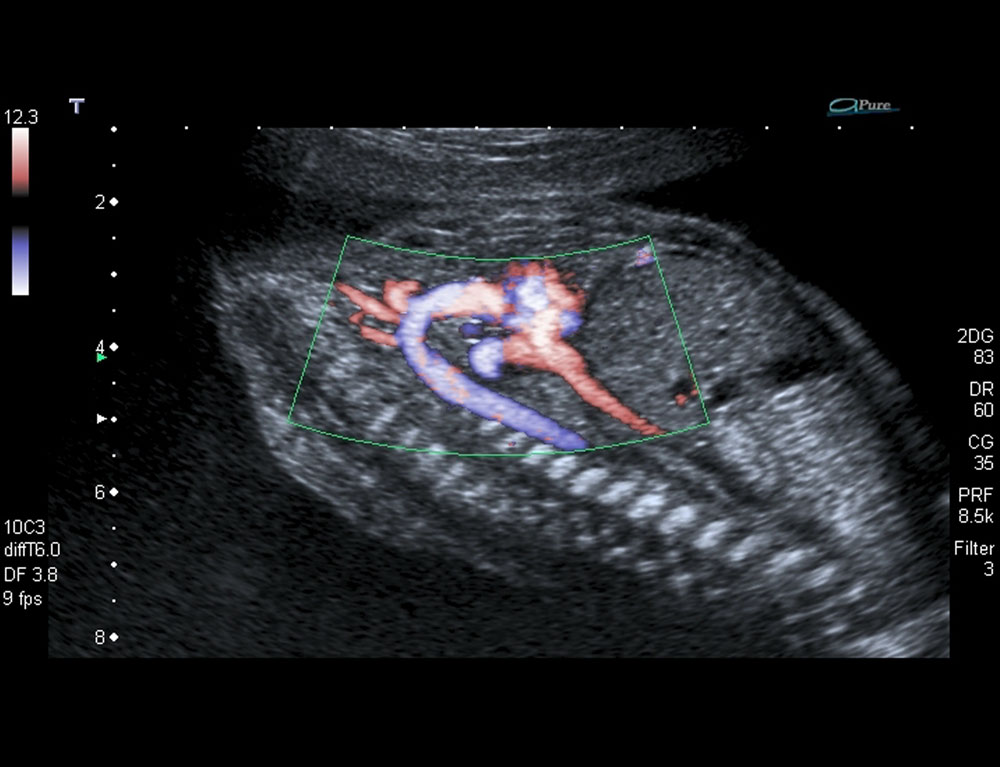

True Hemodynamic Flow.

Advanced Dynamic Flow™ (ADF)*

Canon Medical Systems' exclusive ADF technology provides highly detailed Color Doppler resolution at high frame rates for high resolution of the small blood vessels and complex blood flow with amazing clarity.

*Available on all current systems.

ADF on the Aortic Arch in a Fetal Heart